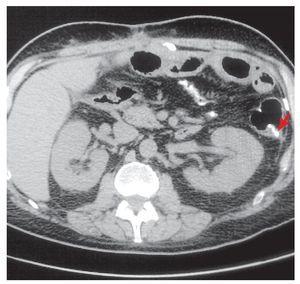

Dos meses después de su egreso, el paciente presentó dolor abdominal de predominio en hipocondrio derecho. Después de realizar ultrasonido de hígado y vías biliares y tomografía computarizada de abdomen, se estableció el diagnóstico de colecistitis aguda alitiásica y calcificación a nivel intestinal por lo que se realizó colecistectomía (Figura 1). Durante el procedimiento se identificó un proceso indurado a nivel intestinal, localizado a 10 cm de la ileostomía a nivel del borde mesentérico. No fue posible hacer el cierre de la ileostomía debido a las múltiples adherencias y al proceso óseo ya descrito. Seis meses después se realizó el cierre de la ileostomía y resección intestinal debido a este proceso óseo, de aproximadamente 10 cm de longitud (Figura 2), misma que se envió a estudio histopatológico que informó inflamación aguda y crónica en ileostomía, congestión vascular y área de metaplasia ósea distrófica asociada a inflamación crónica (Figura 3). El paciente evolucionó satisfactoriamente por lo que fue dado de alta al cuarto día de la cirugía.

¿ Figura 2. Pieza resecada en la que se observa calcificación ósea en el borde mesentérico proximal a la ileostomía.